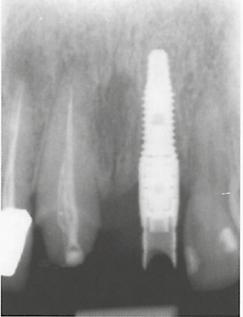

7. ábra: Röntgenfelvétel a UNIT Abutmenttel.

8. ábra: Röntgenfelvétel a UNIT Abutmentre rögzített ideiglenes koronával. Magas Precizitású Implantációs Rendszer9. ábra: A lágyszövetek állapota a varratok eltávolításakor, a műtét Innovatív Komponensekután két héttel.